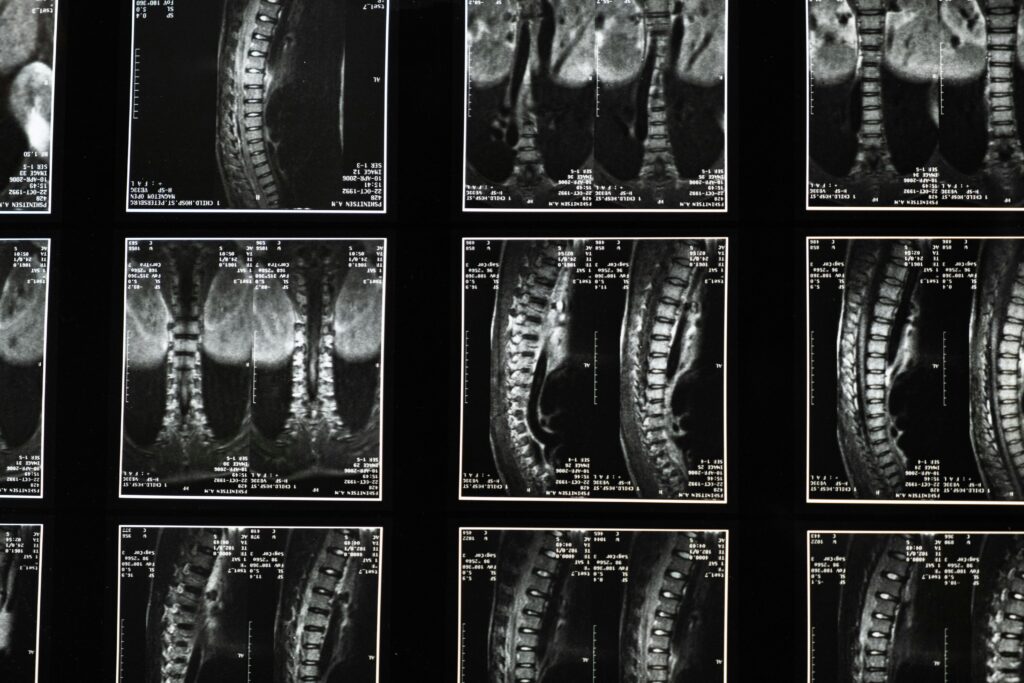

Spinal Injuries

Spinal injuries are common in accidents. Spinal injuries affect people’s necks and backs. The source of the pain can either be from a disc, a facet joint, or the muscles and ligaments. The symptoms can be immediate or delayed.

Spinal injuries can start out as a nagging, persistent pain, but turn into a life-altering disability. Symptoms to look out for include numbness and tingling in the hands and arms if there is a neck injury, and feet and legs if there is a low back injury.